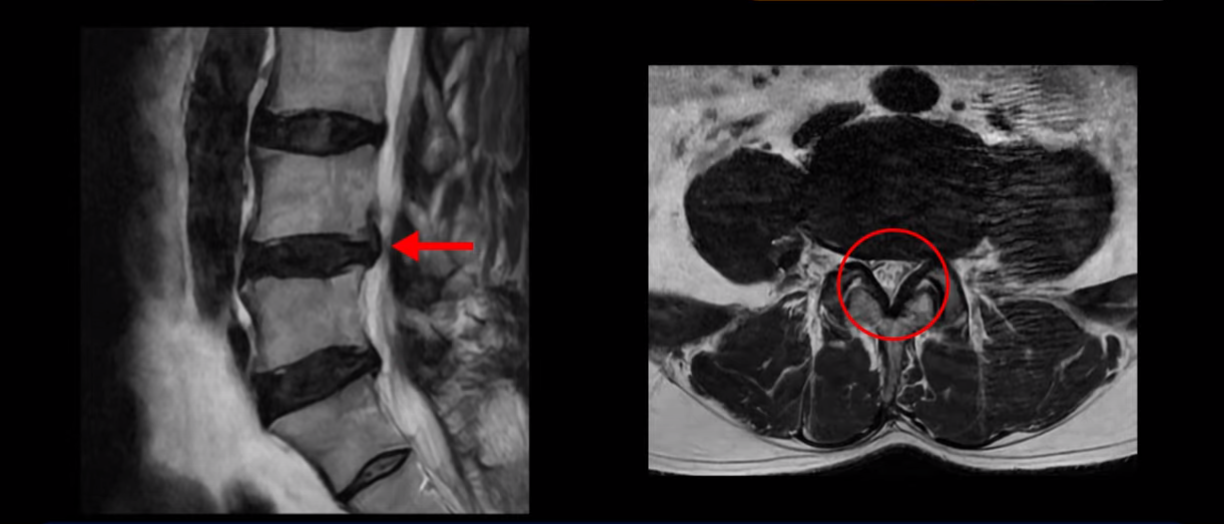

이분은 왼쪽 무릎 아래로 본인 표현으로는 다리를 잘라 버리고 싶다고 할 정도의 심한 통증이 있는데 보통 이런 표현은 디스크 파열이 발생했을 때 많이 사용하는 표현입니다. 이분 4번 5번 디스크를 자세히 보면 왼쪽으로 파열되어 밀려 올라간 디스크 수핵을 볼 수 있습니다.

옆에서도 보이지만 단면에서도 왼쪽으로 심하게 밀려나온 수핵이 잘 보입니다.